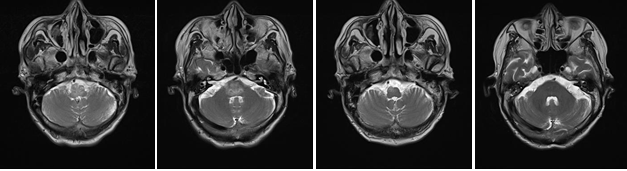

有了家属的这份信任,脑二病区全体医护人员便承担起了全部诊疗重任。考虑患者虽然诊断得的是脑干脑炎,但感染的具体原因还不清楚,是病毒性?细菌性?还是自身免疫性?此时,恰逢新冠疫情期间脑脊液标本不能外送检查,董致郅副主任就查阅文献,完善腰椎穿刺检查、给患者制定详细的中西医结合治疗及护理方案,同时应用抗病毒药物和激素治疗,并加用了脑保护和营养神经药物,根据患者症、舌、脉的变化,先后予醒脑开窍、益气养阴、补益中气等中药汤剂,并及早行针灸治疗。这期间患者先后出现了高热不退、呼吸衰竭、心力衰竭、急性肺水肿、重度低蛋白血症、电解质紊乱等一系列非常严重的并发症,但经过全科人员的共同努力,相继给予呼吸支持、营养支持、脱水降颅压、利尿消肿等措施,患者病情逐渐趋于稳定,神志逐渐转清,经过一个月救治,患者除左侧肢体活动欠利外,其余症状已基本治愈,复查头颅核磁显示桥脑、延髓异常信号已基本消失,复查腰穿脑脊液也未见明显异常。现患者已转入康复科行进一步肢体康复治疗。

治疗前 治疗后